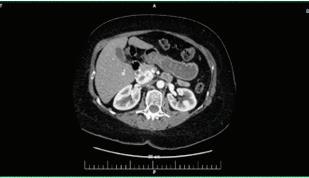

66 БЪБРЕЧНО-КАМЕННА БОЛЕСТЕТИОЛОГИЯ, ЧЕСТОТА, ЛЕЧЕНИЕ И ПРОФИЛАКТИКА В. Василев, Н. Димитров